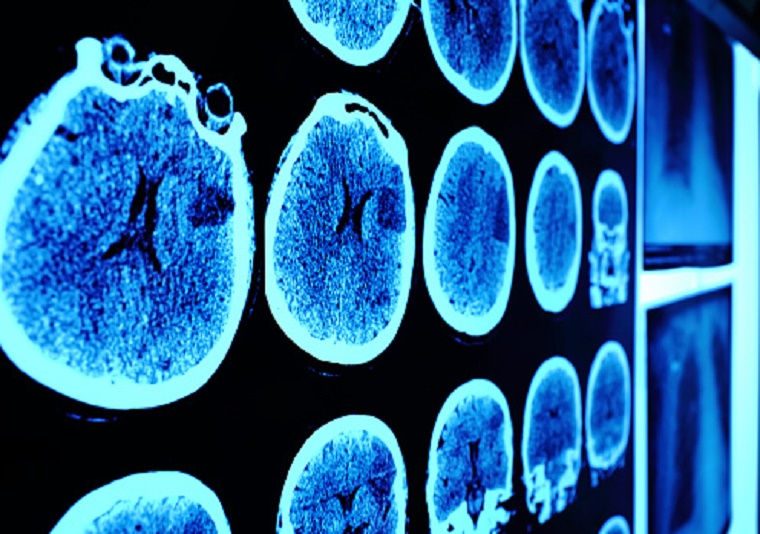

The neuro-oncology program at Atlantic Health brings together a multidisciplinary team of medical experts. These experts bridge the fields of neurology, radiology, radiation oncology, neurosurgery and medical oncology to provide comprehensive care to adults and children with brain tumors including, but not limited to:

Brain-related cancer care

The neuro-oncology program at Atlantic Health provides an integrative and comprehensive treatment approach for those whose cancer involves the brain and nervous system. Our multi-disciplinary team of experts utilize such diverse treatment options as: